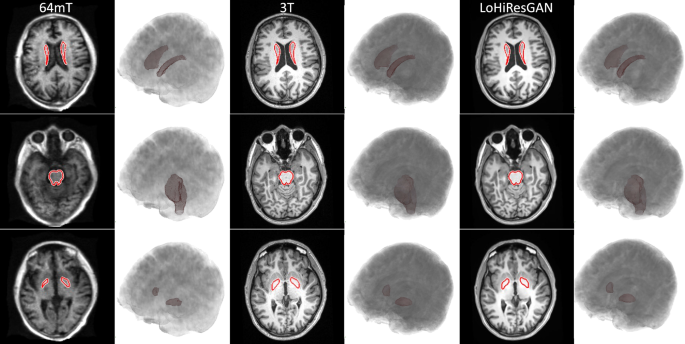

In Fig. 6, T1-weighted images provide a detailed visualization of three specific neural regions-the caudate nucleus (depicted in the first row), brain stem (shown in the second row), and globus pallidus (featured in the third row). Their 3D renderings, based on data from a 26-year-old male participant, further elucidate their structural nuances. A pronounced disparity is evident in the pallidum region between the 64mT and LoHiResGAN images. In contrast, the brain stem and caudate showcase minimal differences across the modalities. Importantly, when focusing on image quality, LoHiResGAN images bear a closer resemblance to the original 3T images, underlining their diagnostic potential.

T1-weighted images showcasing the caudate nucleus, brain stem, and globus pallidus in rows one, two, and three, respectively, with their 3D renderings from a 26-year-old male.